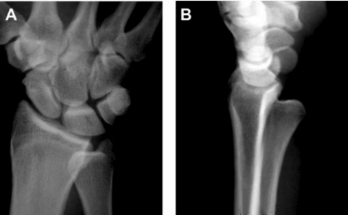

下尺橈關(guān)節(jié)脫位的診斷除依靠損傷機制、臨床表現(xiàn)及影像表現(xiàn)外,某些損傷也可提示存在下尺橈關(guān)節(jié)韌帶的損傷。包括蓋氏骨折、尺骨莖突基底部的骨折及CT橫斷位乙狀切跡的撕脫骨折。

從左到右:

蓋氏骨折、尺骨莖突基底部骨折、乙狀切跡撕脫骨折